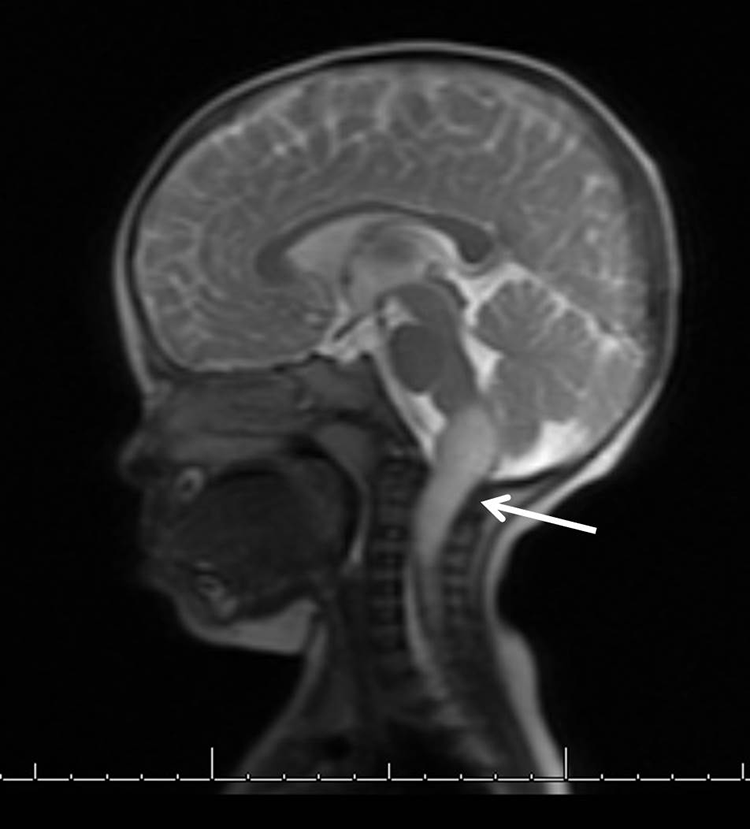

Describe the Radiologic Features in Figure 1

Chest X-ray, left lower extremity X-ray, and hip ultrasound are normal. A BMP, CBC, CRP, and ESR are normal. Computed tomography imaging of the head demonstrates an incompletely imaged expansile lesion involving the medulla/upper cervical spinal cord. Follow-up MRI of the brain confirms an intraparenchymal expansile mass (4.6 × 1.9 × 1.9 cm) with T2 hyperintensity and heterogeneous enhancement in the medulla extending inferiorly into the cervical cord to the upper C4 level (Figure 1). The imaging studies are negative for other lesions.

Sagittal T2 brain MRI with an intraparenchymal mass highlighted by the white arrow. MRI indicates magnetic resonance imaging.